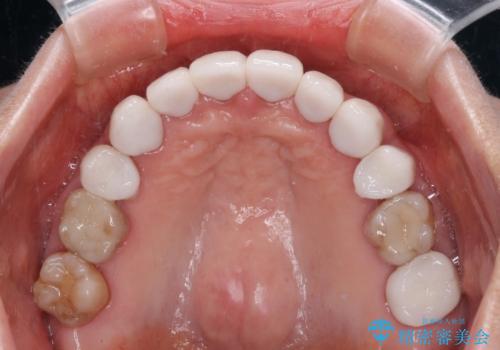

- 口元の突出感と歯の色を気にして来院された患者様です。

口元を引っ込めるために上下左右第一小臼歯4本を抜歯し、ワイヤー矯正を行うこととしました。

歯の色はホワイトニングかセラミッククラウンで対応することとしましたが、ブラックトライアングルが目立つことが予想されたため、目立つ範囲をオールセラミッククラウンで補綴することとしました。